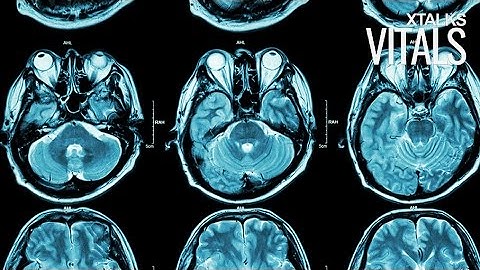

Validating Concussion Through Brain Imaging